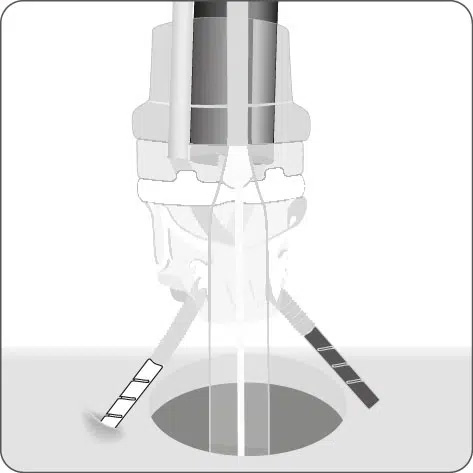

Einführen der Anker in den Endoskop-Arbeitskanal und den inneren BARS® Arbeitskanal.

Überkreuztes Platzieren der Anker im vorbereiteten Zielgewebe.

Platzieren des Kalibrierballons in der Anastomose. Schrittweises Einziehen des Gewebes in die BARS® Applikationskappe, mit abwechselnden Zugbewegungen.

Sicherstellen, dass das Gewebe symmetrisch in der Kappe positioniert ist. Platzieren des BARS® Clips durch Drehen des Handrads.